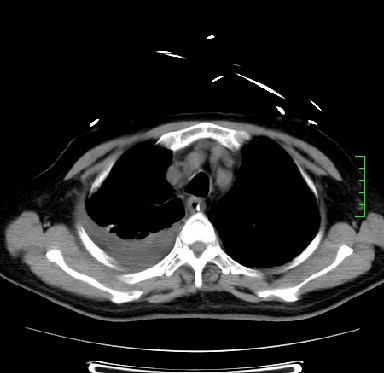

icu病人,几天都没明确诊断。m,76y,咳嗽、咳痰1周,伴气促,右胸痛入院,pe:t38.3c p135 r25 bp135/85。双肺可闻及大量湿罗音,心、腹未见明显异常。诊断:1心衰?2肺部感染?3冠心病?

9号平片

11号ct